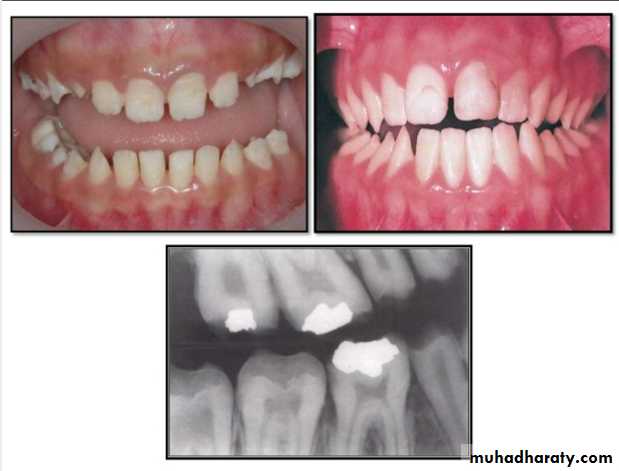

Hypodontia

Oligodontia

Anadontia

Developmental absence of all maxillary premolars and both mandibular second premolars. Note the retention of the maxillary primary canine as a result of the posterior position of the maxillary permanent canine.

CAUSES: may be the result of numerous independent pathologic mechanisms that can affect the orderly formation of the dental lamina (e.g.,orofaciodigital syndrome), failure of a tooth germ to develop at the optimal time, lack of necessary space imposed by a malformed jaw, and a genetically determined disproportion between tooth mass and jaw size.

*Mild hypodontia by orthodontics.

*Severe cases by restorative, implant, and prosthetic procedures .